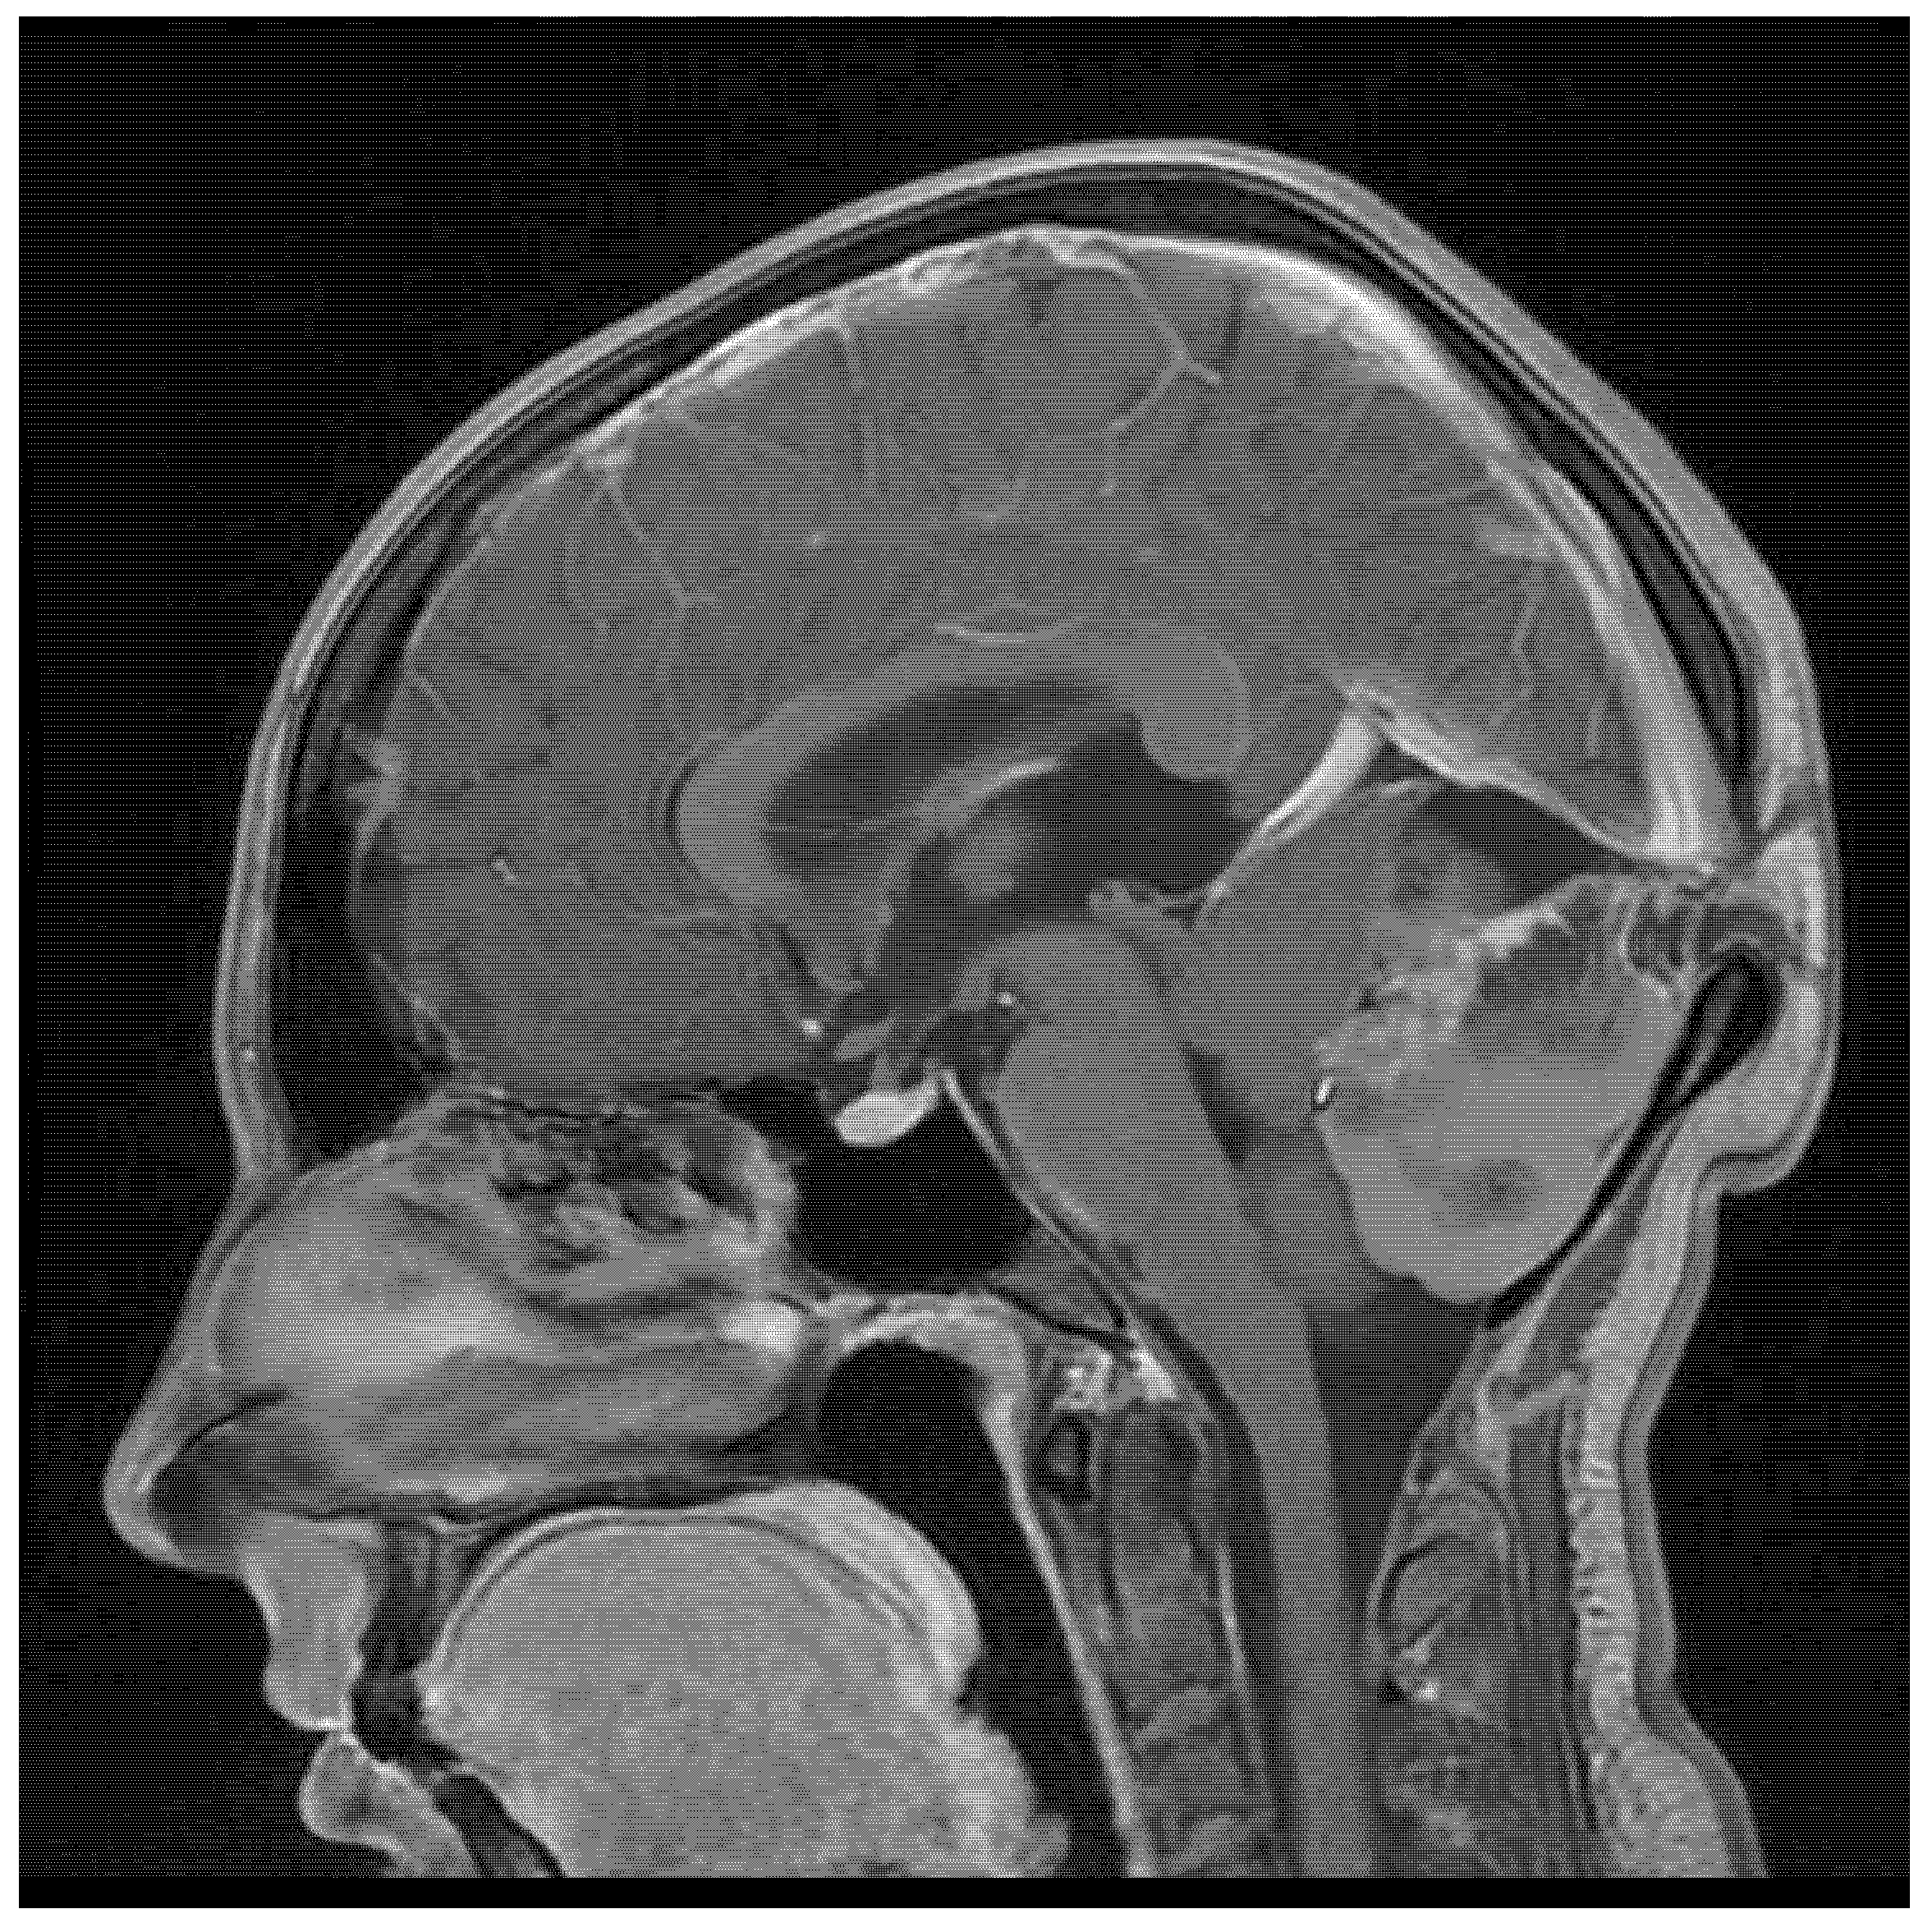

| 22/female | cerebellum—midline | mature teratoma | severe headache | current case |